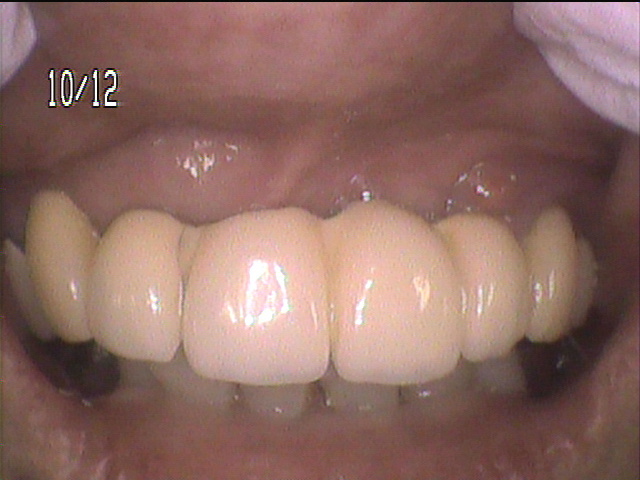

治療後写真

- 「目立たない義歯」を装着した状態です。

金具が無いので、良く見ないと義歯を装着していることは分かりません。

- 内側には薄い金属のプレートが入っているので、奥歯でしっかり固定されています。